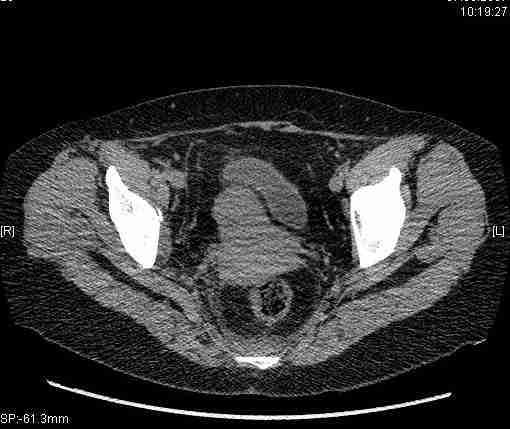

Re: Т-образный перелом вертлужной впадины

Удалось сегодня вывести пациентку в соседнюю больницу, где есть кт. Срезы сделаны только горизонтальные.